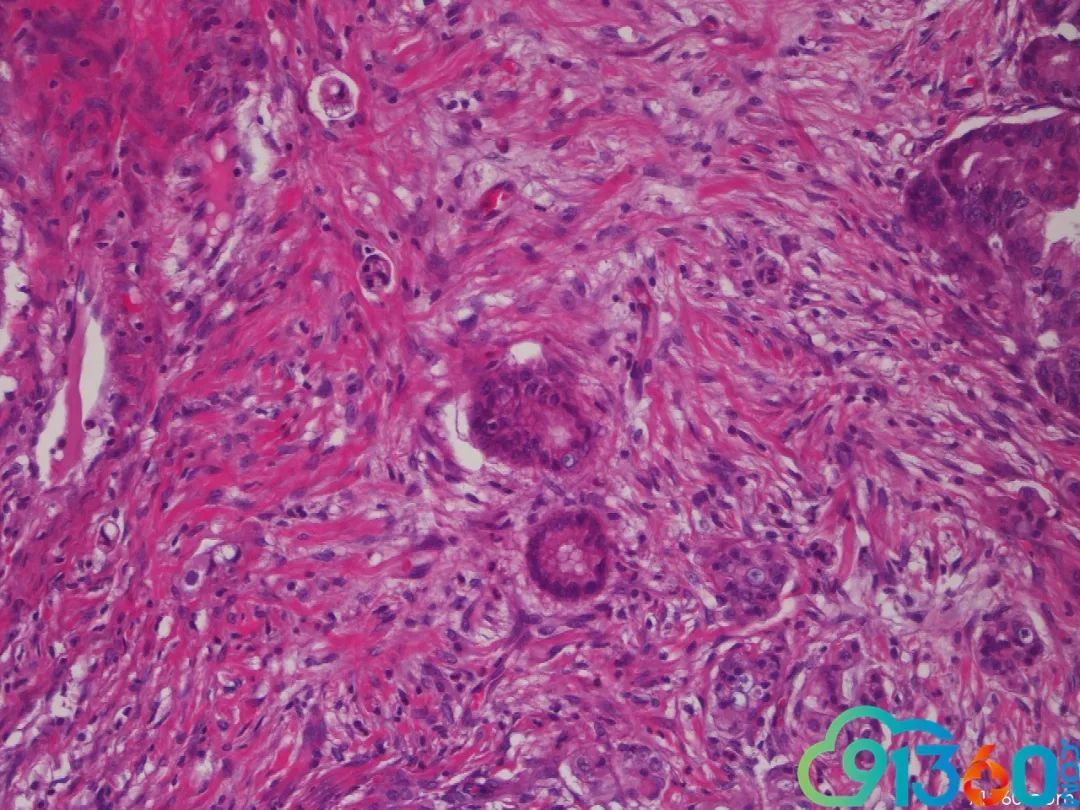

令人头痛的阑尾粘液癌

阑尾粘液性肿瘤

好多新同志没见过阑尾粘液腺瘤,现在分享一下 希望哪怕有一点点帮助